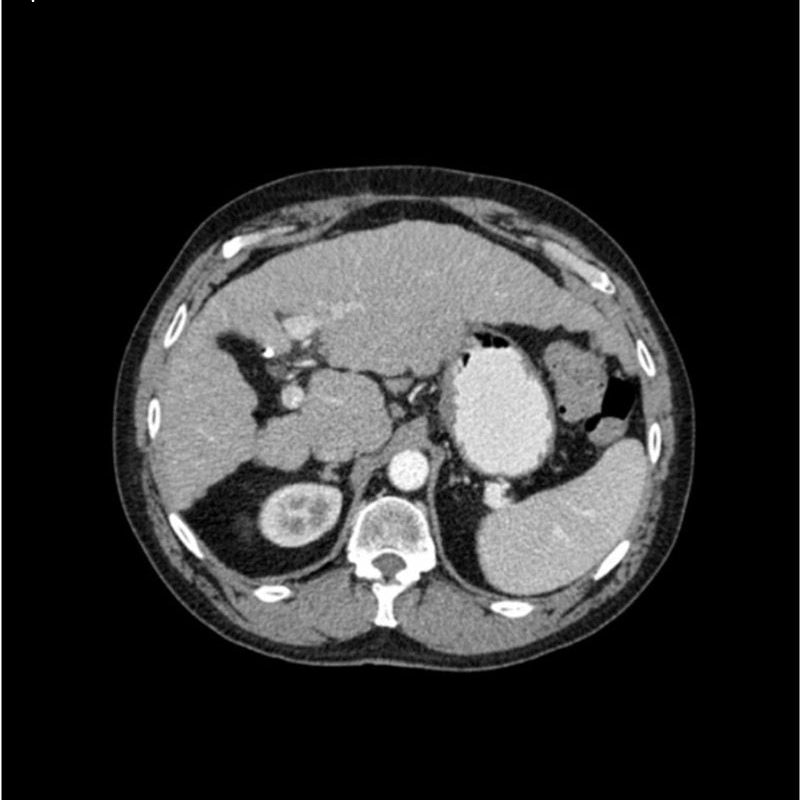

abdomen in portal venous phase. It covers the tenth thoracic vertebra to the third lumbar vertebra. The phantom represents an abdomen after cholecystectomy with small clips. The liver has typical signs of cirrhosis and there is an inferior vena cava filter implanted at the level of the third lumbar vertebra. Both kidneys have cystic lesions and there is a small kidney stone on the left side.

Realistic simulation of vasculature, bone and soft tissues, including the liver, pancreas, spleen, adrenals, kidneys, stomach, small intestine and colon.

- Liver cirrhosis

- cholecystectomy

- inferior vena cava filter

- kidney cysts

- kidney stone

- lymph nodes.